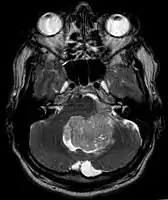

- Ependymoma of 4.ventricle in MRI.